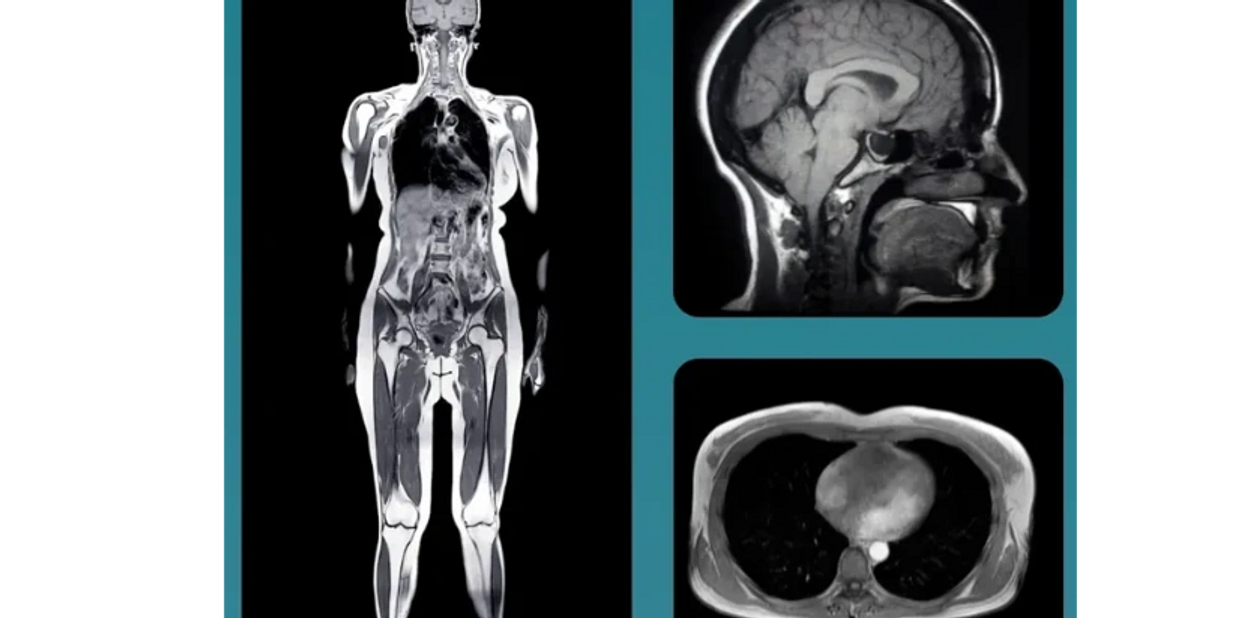

Whole body MRI is a fast (under 1 hour), safe, and non-invasive (no contrast) way to catch stage one cancers, aneurysms and hundreds of other conditions, largely before symptoms present.